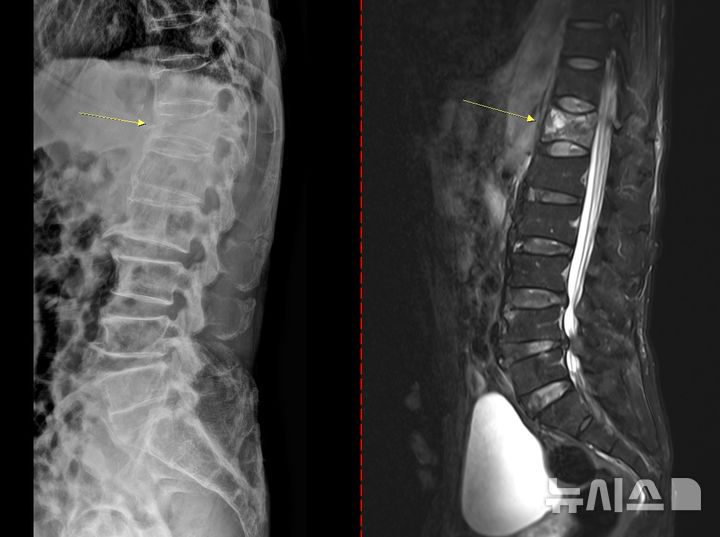

골다공증은 초기 징후가 뚜렷하지 않아 특히 주의해야 한다.통증이나 자각 증상이 거의 없다가 시간이 지나 가벼운 충격만으로도 손목이나 대퇴골(엉덩이뼈)이 골절되면서 뒤늦게 진단되는 경우도 있다.때로는 등이 굽거나 키가 줄어드는 척추 압박골절이 나타날 수도 있다.심할 경우 허리를 구부리거나 기침을 하는 등 일상생활 중에도 뼈가 쉽게 부러질 수 있다.

치료 없이 방치하면 뼈는 점점 약해지고 척추와 손목,대퇴골 골절 등 중대한 골절이 발생할 수 있다.특히 대퇴골 골절은 고령 환자에서 수술 후 합병증,장기 입원,사망률 증가와 직결되는 중증질환이다.척추 압박골절의 경우 자세 변화,비너스 토토만성 통증,비너스 토토보행 장애를 유발해 ▲활동량 감소 ▲근력 저하 ▲추가 골절의 악순환으로 이어진다.